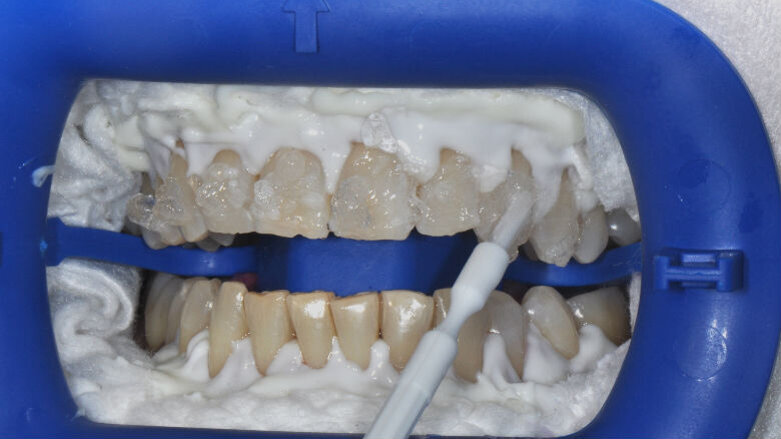

- Isolamento del campo operatorio: applicare la diga liquida su tutta la gengiva e polimerizzare;

- Applicazione del gel Zoom su tutto lo smalto;

- Attivazione della lampada Zoom;

- Al termine di ogni ciclo da 15 minuti, rimozione del gel con aspiratore e applicazione di nuovo gel Zoom.

- Applicazione del Whitening Accelerator PH Booster su tutto lo smalto;

- Applicazione del gel Zoom; senza sciacquare il Whitening Accelerator PH Booster fino a 4 cicli massimo;

- Attivazione della lampada Zoom.

- Al termine di ogni ciclo da 15 minuti, rimozione del gel con aspiratore e applicazione di nuovo Whitening Accelerator PH Booster seguito da gel Zoom.